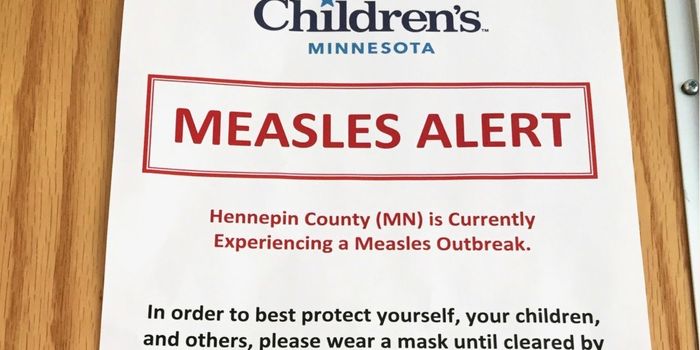

JAN 12, 2015VideosHealth officials fear thousands may have been exposed to the measles at Disneyland and "Disney California Adventure" las ...